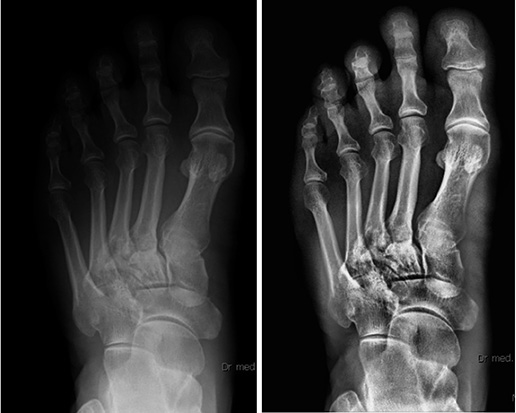

Zgodnie z wcześniejszymi zapowiedziami zakończono próby kliniczne detektora Xrpad. Dwa lata temu producent oprogramowania digipaX zaprezentował nowe rozwiązanie – MagicSharp – regulowany filtr wyostrzania zdjęć z dowolnych systemów cyfrowego obrazowania RTG. Widoczny przeskok jakościowy był tak duży, że pojawiały się pytania o przyszłość. Czy można zrobić coś więcej? Można. Postęp w technice jest nie do…